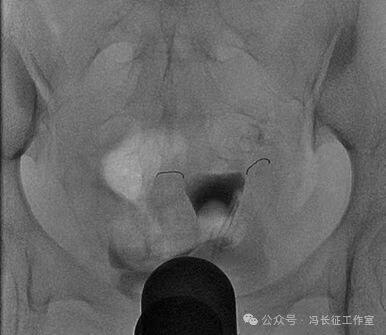

2013年在胃肠机上点片的造影片可以明确显示双侧输卵管间质部和峡部细,长度约4厘米。

微信图片_20240223171114(1).jpg